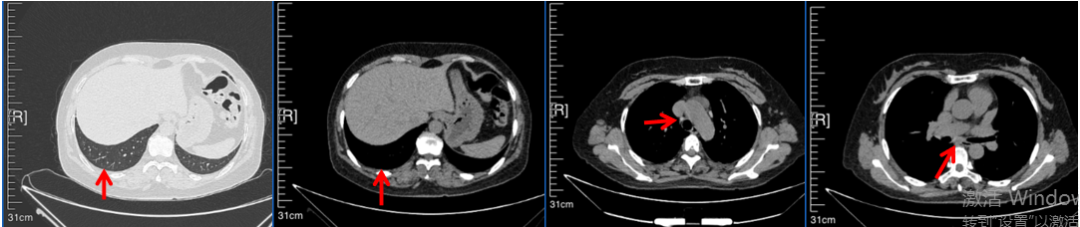

2016年1月复查CT提示支气管截断可见新发小结节,一线治疗采用培美曲塞+DDP方案化疗4周期(培美曲塞3.36,DDP 480mg)。化疗后复查胸部CT:右肺见不规则结节样影,最大层面大小约19mm*8mm,较前比较明显增大,疗效评估PD。2017.3-2017.4予单药多西他赛化疗3周期,疗效评估SD。2018年5月末复查CT提示结节较前增大,评效为PD,2018年6-10月予多西他赛+CBP化疗4周期,疗效评估SD。2022年5月患者出现活动后气短,复查胸部CT示右肺膨胀不良;右侧胸腔积液增多。胸腔积液包埋病理示符合肺腺癌细胞。行NGS基因检测:EML4:exon13-ALK:exon20融合。PD-L1(克隆号22C3)TPS<1%。

2018.07

2022.05

2022.08

2023.05